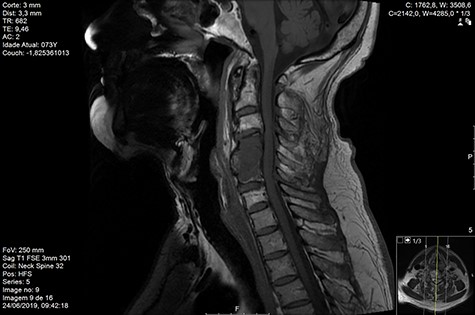

Computed tomography (CT) (Figs 1–3) and magnetic resonance imaging (MRI) (Figs 4–6) of the cervical spine were performed and revealed a lytic lesion involving most of C4, C5 and C6 vertebral bodies with bilateral extension to the posterior spinal elements of C4 and C5 and complete disruption of C4-C5 and C5-C6 intervertebral discs.

MRI and CT scans performed at 90 days post-radiation therapy showed an arrest of further progression of instability and resolution of the lytic lesion (Figs 7–13).